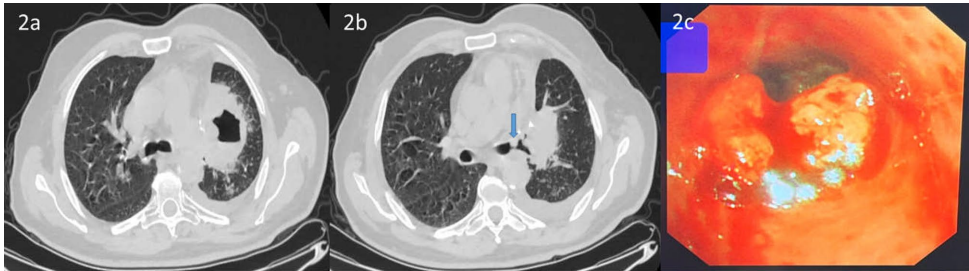

某医疗机构的研究团队在《BMC Pulmonary Medicine》发表的研究,通过3例典型病例的系统分析,为这一临床困境提供了重要见解。研究纳入3例因气道阻塞出现严重呼吸困难的患者,其中2例为冠脉支架术后,1例为外周动脉支架术后,均需持续DAPT治疗。研究团队在完备的止血准备下,使用1.8 mm活检钳实施EBB,所有病例仅出现1级出血(轻度出血仅需吸引),最终均成功获得病理诊断(2例鳞癌,1例肺腺癌复发),未发生严重并发症。

关键技术方法包括:① 局部应用4℃冷生理盐水和稀释肾上腺素(1:10,000)预防出血;② 使用Fujinon EB-530T支气管镜配合1.8 mm活检钳精确取材;③ 持续心电监护下操作;④ 预先备齐止血球囊、介入放射学支持等应急方案。病例均来自临床急症队列,具有明确的手术指征。

研究对比了不同支气管镜操作的出血风险谱:经支气管肺活检(TBLB)风险最高(89-100%出血率),而EBB风险仅约0.43%。尽管Ernst等证实TBLB在氯吡格雷期间禁忌,但本研究表明EBB在充分准备下可行。关键预防措施包括:① 避免活检外周肺组织;② 近端支气管局部用药减少全身吸收;③ 使用低相互作用风险的PPI(如泮托拉唑)。